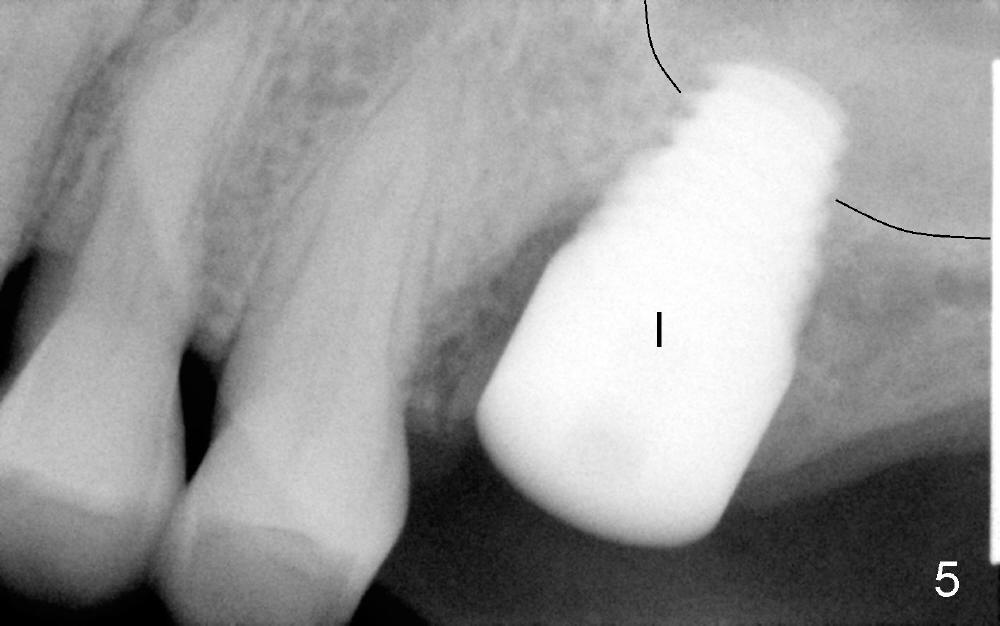

Extraction turns out to be simple with sectioning. After debridment of the socket and soaked with Clindamycin, the ostoeotomy forms using osteotomes, followed by insertion of a tap (Fig.4 T, 6x14 mm). After adjustment of the trajectory (Fig.4 arrow), larger taps are used (7x14, 8x14 mm) before placement of a 8x14 mm implant (Fig.5 I). There is small gap (Fig.6 arrowheads) around the implant. The wound is protected by perio dressing (Fig.7). The dressing is removed 7 days postop. Fig. 8 taken 2 weeks postop shows that the peri-implant gap has closed.